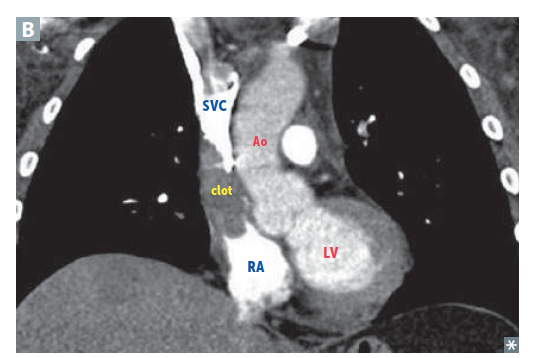

Headaches, dizziness, increased risk of aneurysm/ rupture of intracranial arteries from impaired blood drainage from the head (facial plethora)

Superior Vena cava syndrome